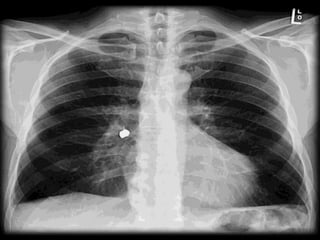

 Chest x ray

 Ct chest